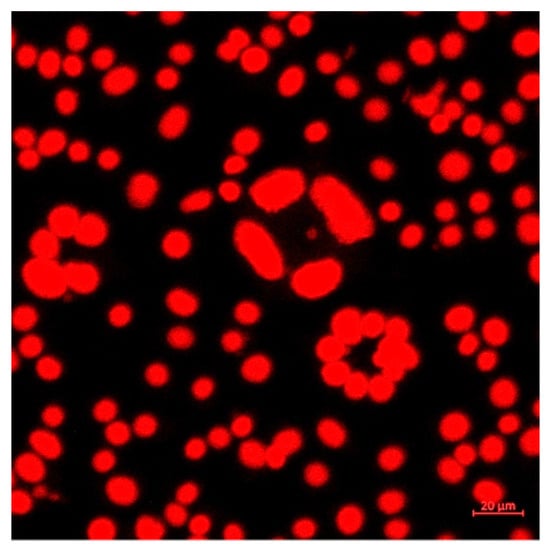

Confocal microscopy was used for the imaging of the cells after exposure to different concentrations of the CURC-loaded gel microemulsion proposed for topical administration. L929 mouse fibroblasts (ATCC) were used as model cells to evaluate the interaction and cytotoxicity of the investigated samples, based on the LIVE/DEAD assays, using calcein AM (LIVE/DEAD Viability/Cytotoxicity Kit for mammalian cells, Life Technologies, Carlsbad, CA, USA) and propidium iodide (PI) (Sigma Aldrich, Merck Group, Darmstadt, Germany). The cells were seeded at an initial concentration of 1 × 105 cells/mL in 24-well plates, and then maintained for 24 h in a culture medium and incubated for 48 h with the gel microemulsion samples (F1.4 as a reference formulation without the drug and F1.4NH1 with encapsulated CURC). The cell cultures after incubation with the treatment were maintained for 30 min at room temperature with 2 µM calcein AM and 1 µg/mL propidium iodide. Viability was assessed using confocal fluorescence microscopy on a Zeiss LSM 880 system (Carl Zeiss AG, Jena, Germany) with 488 and 514 nm lasers. The acquired images were processed using ZEN 2.3 software (Zeiss, Jena, Germany).

3.2. Physical Characterization of Winsor IV Microemulsions

Due to the fact that a Winsor IV microemulsion is a transparent one-phase system, it is easy to differentiate it from Winsor I, II and III microemulsions or non-microemulsion systems. The compositions of the single-phase microemulsions are presented in Table 1. Because a Winsor IV microemulsion can be confused with a liquid crystal based only on the visual appearance, an additional analysis must be performed. The transparent one-phase systems were inspected using cross-polarized light microscopy to confirm whether they were Winsor IV microemulsions. Microemulsions are isotropic; thus, they do not interfere with polarized light [44]. A cross-polarized microscopy analysis confirmed the isotropic nature of all the six samples selected for the study.